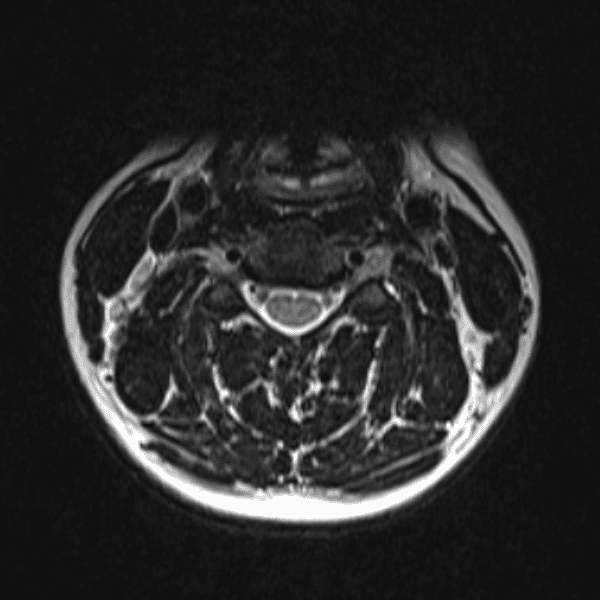

Simulates call by including subtle or difficult cases and some normals.

35 cases